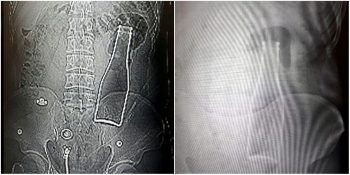

Zaman zaman tuhaf durumlarla karşılaşabiliyoruz. Bazen insanlar pika sendromu nedeniyle farklı nesnelere...